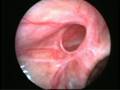

Can this operation done by laparoscopy?

Operation in hernia involves closing of the open passage through which the testis has come down. This can be done from outside as in open surgery or from inside by laparoscopy. If your child has got a hernia on one side, there is a 15 – 25 % chance that he / she may develop a hernia on the opposite side at a later date. With the help of laparoscopy we are able to look at the opposite side to see if the passage is open on that side as well. This can be closed at the same sitting if you wish to. Recovery from surgery, timing of surgery and discharge from hospital are the similar for open surgery and laparoscopic surgery.

However, it is important to note that an open passage does not always mean that your child will get a hernia. There is no harm in opting for a second surgery later if your child at all develops a hernia on the opposite side.

Laparoscopic repairs have a slightly higher chance of recurrence (i.e. the hernia coming back again) as compared to open hernias. You can discuss the pros and cons in details with your doctor when you come for consultation.